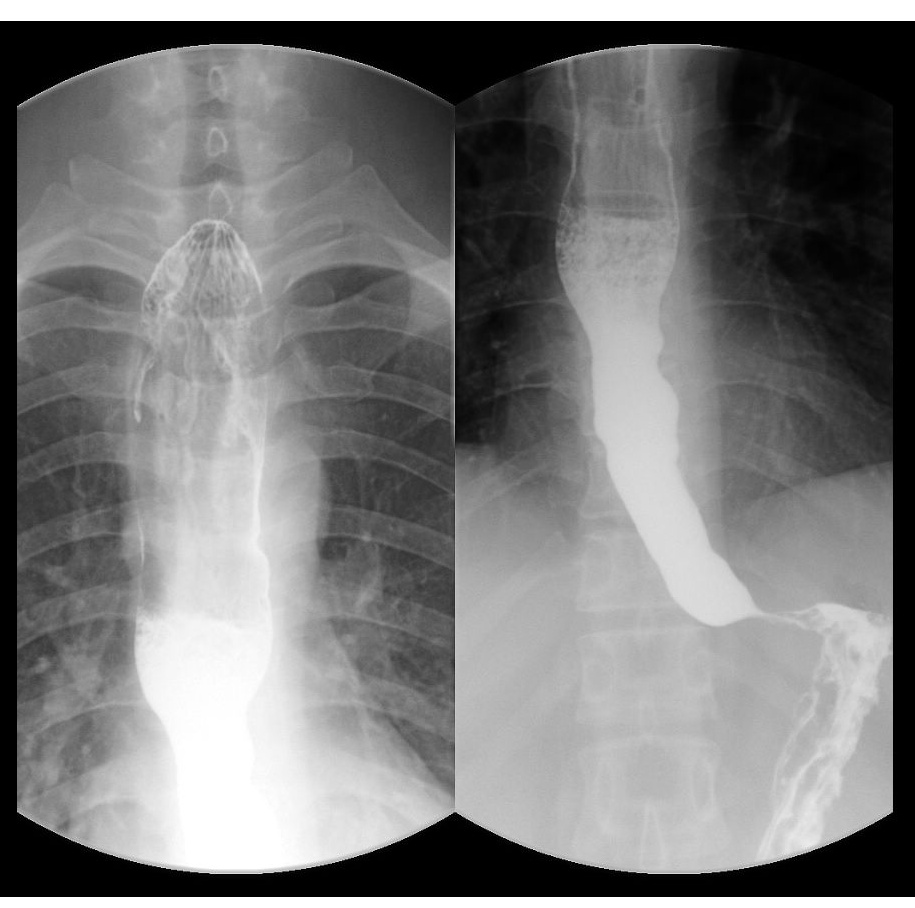

近日,高宇来到江苏大学附属医院江滨医院消化内科就诊,经胃镜及上消化道造影检查,提示食道扩张明显,贲门狭窄呈鸟嘴样改变,而这些正是贲门失弛缓症的典型表现。

上消化道造影提示食管明显扩张,贲门鸟嘴样狭窄